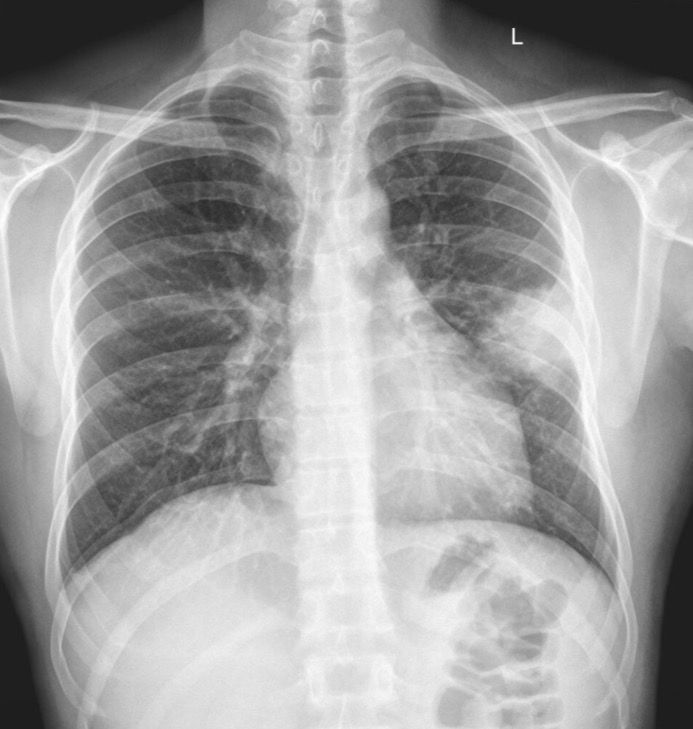

55-year-old male is a smoker presents with chest pain. Fever and cough. Clinicians are worried about seeing cancer on a chest x-ray.

Opacity on xray, air bronchogram needed next

What does this air bronchogram indicate for the pt

Solid upper left lobe “hepatization”. Pt has lobar PNA